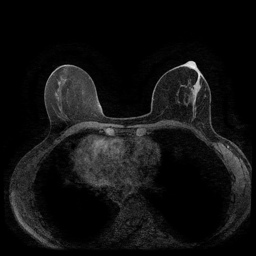

MRI images. The data used in this study are from the DUKE Breast Cancer Dataset [23], a comprehensive single-institutional retrospective collection of 3D MRI scans from over 900 patients with biopsy-confirmed invasive breast cancer at a university hospital. Each study includes a 3D MRI acquired using 1.5T or 3T scanners, from patients in the prone position. On average, each 3D scan consist of 250 2D slices (see Figure 1). For the predictive tasks, the slices are categorized into two groups: those containing breast tumors and those without. Following the approach of [15, 12], we establish a buffer zone between slices containing tumors and those that do not (highlighted in yellow in Figure 1(a)). Images within this buffer zone are excluded from analysis, and the remaining slices are labeled and used for the predictive task.

Magnetic field strength. 3T scanners offer higher magnetic field strength, improving signal-to-noise ratio (SNR) and image resolution for sharper, more detailed images [24]. However, they are more prone to artifacts, heating effects, and signal loss, especially around metal implants [5]. As such, our proposed dataset involving this spurious signal features a non-local spurious signal that influences the entire image rather than a localized region. An example set of images obtained from 1.5T and 3T devices are provided in Figure 3, showing that it is visually not possible to distinguish 1.5T MRIs from the 3T ones.